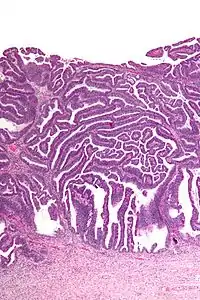

| Micrograph of a villoglandular adenocarcinoma the cervix. H&E stain. | |

The name of the lesion describes it microscopic appearance. It has nipple-like structures with fibrovascular cores (papillae) that are long in relation to their width (villus-like), which are covered with a glandular pseudostratified columnar epithelium.

Very low magnification